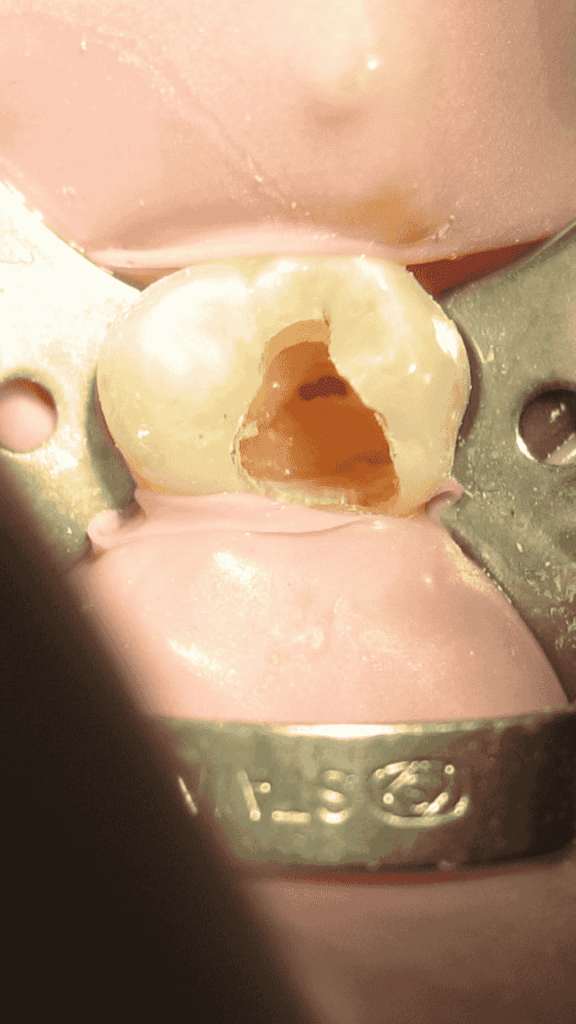

The 5/100 tapered Flare design allows clinicians to apply controlled lateral pressure during obturation, optimizing gutta percha placement without causing canal deformation. The conical tip ensures accurate insertion and guidance within the canal, helping to condense gutta percha efficiently along the canal walls.

The tapered body of the spreader is specifically designed to match accessory-sized gutta percha points, making it ideal for lateral condensation techniques — a widely used method for filling root canals.

After cleaning and shaping, the spreader is used to create space for accessory gutta percha cones alongside the master cone. This ensures dense lateral compaction, reducing voids and improving the seal of the root canal system.

🔹 3. Retreatment Cases

During retreatment, after removal of the old filling, these spreaders help in re-obturation by ensuring uniform lateral pressure and a tight, well-adapted fill — essential for sealing accessory canals and preventing microleakage.